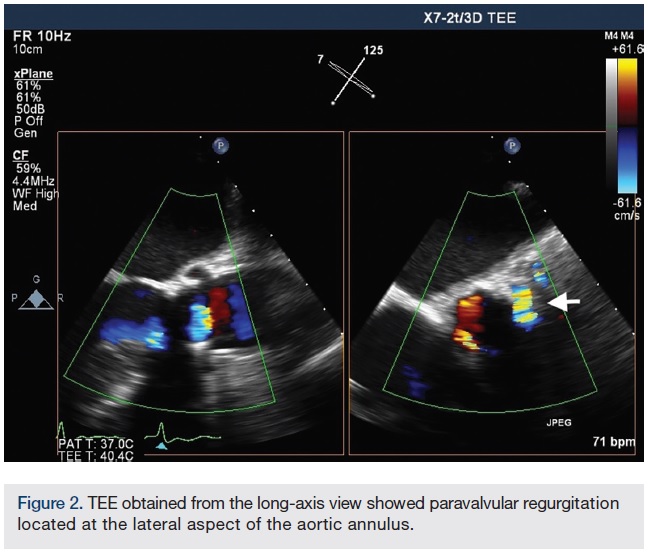

The procedure was performed under deep sedation with use of intravenous (IV) propofol. Transesophageal echocardiography (TEE) was utilized to assist in the closure of the aortic paravalvular leak (PVL). TEE confirmed a bioprosthetic aortic valve with mild central intrinsic regurgitation, and moderate to severe paravalvular regurgitation (Figure 1A-B). The paravalvular regurgitation was found at the lateral aspect of the aortic annulus (Figure 2).